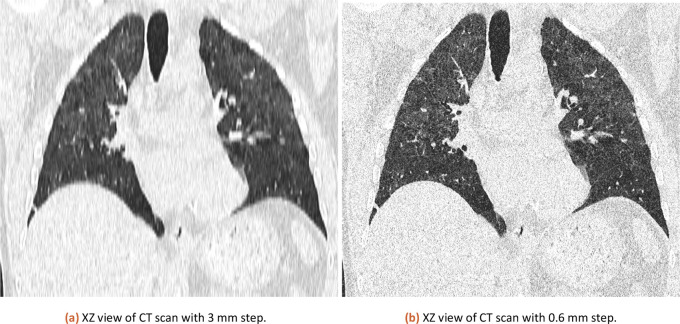

现代治疗是基于对现有数据的可重复的定量分析。Covid-19大流行确实加速了几个多学科领域的开发和研究。其中之一是使用软件工具进行更快和可重复的患者数据评估。CT扫描对于搜索细节是无价的,但在3D数据中看到全局并不总是那么容易。即使在CT逐层的视觉分析中,内部和内部的变异性也会产生很大的差异。我们介绍了与学院医院放射学中心Královské Vinohrady共同开发的ImageJ工具,用于对COVID-19患者进行CT评估。开发该工具是为了帮助估计受感染肺部的百分比。将患者按百分率分为五组,采取相应的治疗措施。

Modern treatment is based on reproducible quantitative analysis of available data. The Covid-19 pandemic did accelerate development and research in several multidisciplinary areas. One of them is the use of software tools for faster and reproducible patient data evaluation. A CT scan can be invaluable for a search of details, but it is not always easy to see the big picture in 3D data. Even in the visual analysis of CT slice by slice can inter and intra variability makes a big difference. We present an ImageJ tool developed together with the radiology center of Faculty hospital Královské Vinohrady for CT evaluation of patients with COVID-19. The tool was developed to help estimate the percentage of lungs affected by the infection. The patients can be divided into five groups based on percentage score and proper treatment can be applied.